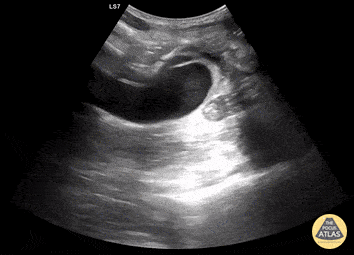

Aortic Endograft Leak - Dr. Lindsay Howe Dr. Tim Scheel Dr. Paul Pelletier

https://www.thepocusatlas.com/aorta